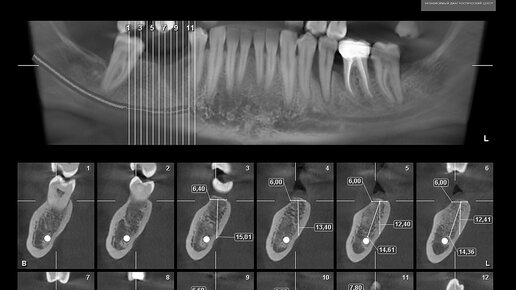

Перед серьезным стоматологическим вмешательством, например, перед дентальной имплантацией, необходимо выполнить сверхточные 3D-снимки. Но иногда можно обойтись и двухмерным изображением. Панорамный снимок более информативен, чем прицельный, поскольку на изображении видно не 1-2 зуба, а обе челюсти с окружающими тканями. Разберем, зачем делают панорамный снимок зубов, есть ли у метода противопоказания и можно ли проходить исследование детям. Где делают панорамный снимок зубов Эффективность стоматологического лечения во многом зависит от диагностических мероприятий...